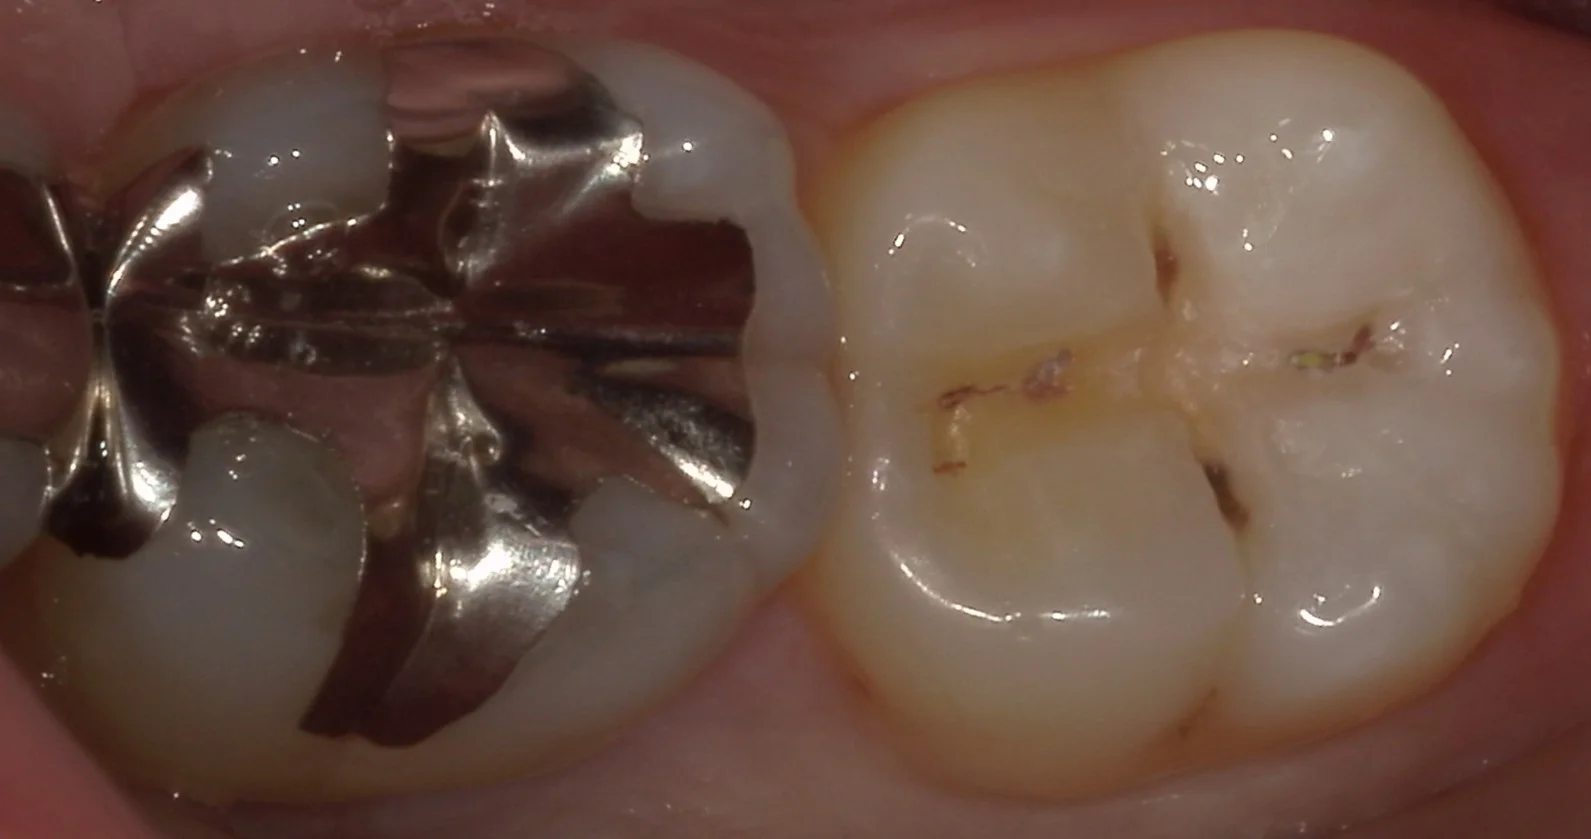

さて、そして詰め物だけ外したのがこちらです。

透けて見えていた部分はそこまで深くありませんが、画面の上下に位置する黒い部分。

ここが非常に深かったです。